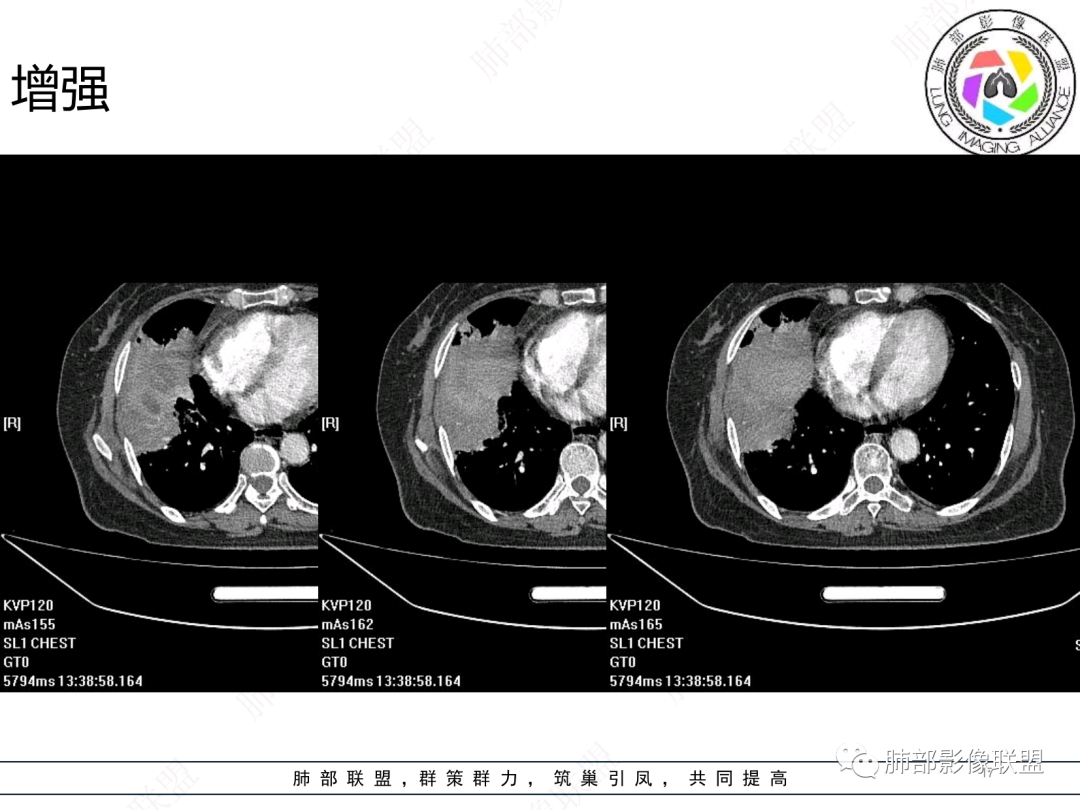

女,74岁,咳嗽咳痰加重一周入院,右肺中叶大片实变影,边界清晰,病灶内密度不均匀,右肺中叶支气管变窄,增强扫描病灶明显强化,考虑恶性病变能,鉴别肺脓肿。

右肺胸膜下实变,跨叶,形态不规则,局部边缘膨隆,中叶支气管外侧段进入后阻塞伴不张,不均匀强化,其内坏死边界欠清晰,复查无吸收,考虑腺癌,鉴别慢性炎症伴脓肿

右肺大片状高密度灶,跨叶,密度不均,边缘膨隆,支气管阻塞,粘液栓,不均匀强化,其内坏死边界欠清晰,复查无吸收,考虑腺癌,鉴别慢性炎症,脓肿

胸部CT:右肺中下叶大片实变影,界清,边缘膨隆为主,中叶外侧段支气管截断。增强不均匀强化,边缘可见血管影迂曲模糊,内见条带状低密度影。治疗后病变进展。考虑恶性,鳞Ca?鉴别TB、OP。

南边:跨叶、楔形/边缘平直、支气管壁无破坏/连续/局部无膨大、实变区肺动脉走形自然、实性部分均匀、延迟强化、坏死腔内壁光滑/内壁强化环/近端与支气管相通,这些点均支持炎性。所以综合分析:符合炎性。